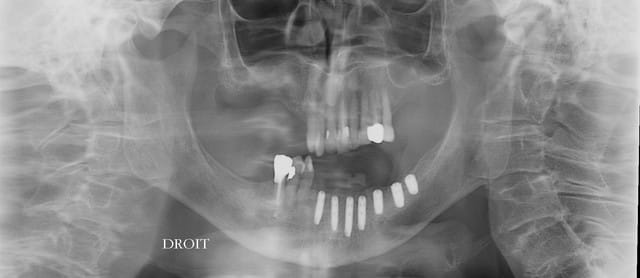

le pano